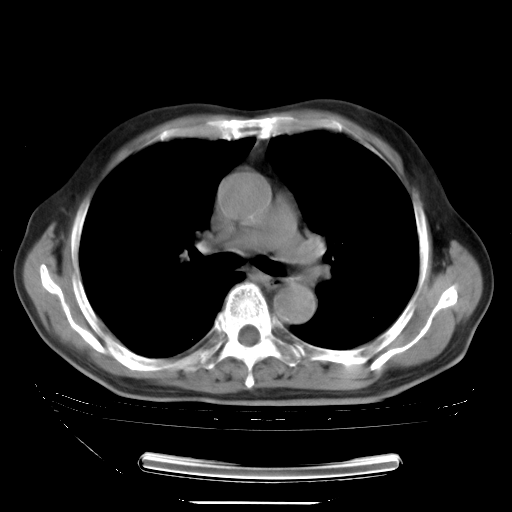

胸腹部CT,诊断意见:左上肺叶钙化灶、左侧胸膜局限性增厚并钙化、胆囊炎。描述部分肺组织呈磨玻璃样改变。

今天复查肺部CT,发现双肺广泛磨玻璃样改变。所以我把3月19日和5月9日相隔50天的肺部CT上传。请大家会诊。

2009年3月19日肺部CT片。

2009年3月19日肺部CT